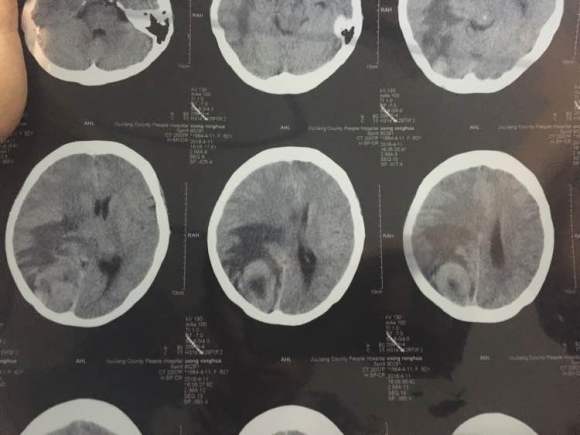

Fiona 02022-03-11 患者家属我妈妈前几天在武汉协和医院做的增强ct结果,医生说大概率是肺癌,准备下周二穿刺,大家能帮我看看嘛,我一点不懂,如果是肺癌...